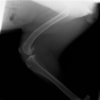

術前左後肢側面像

術後左後肢側面像

術前のTPAは左後肢33.1°右後肢26.8°でしたがTPLO実施により左後肢5.5°右後肢12°に矯正されました。